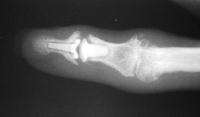

Clinical Example: Distal Interphalangeal Joint Arthroplasty with reversed Ascension carbon implant arthroplasty

These two cases illustrate the use of the Ascension PIP joint implant arthroplasty in the DIP joint position. The stem of the distal component is too wide to fit into the typical distal phalanx, but the proximal component stem will, and in selected cases, the implant will fit in this position if it is placed in a reversed proximal-distal position. These cases illustrate this technique - not as an endorsement, but as a demonstration of  technical feasibility. At one year, each  reconstructed joint was painless and had about 30 degrees range of motion.

Distal interphalangeal erosive osteoarthritis severe enough that the diagnosis of giant cell or other tumor was suspected. Fortunately, no tumor was encountered at surgery.